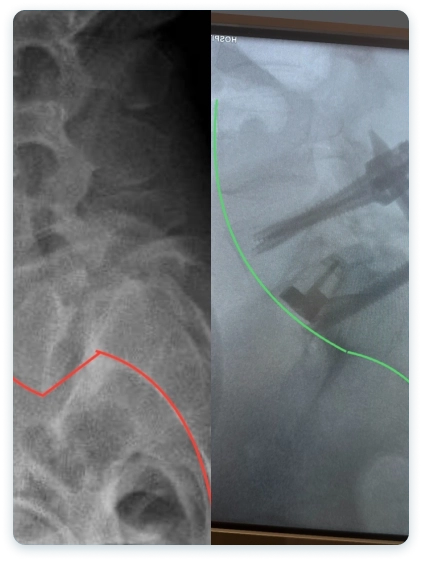

Veja casos de antes e depois dos meus pacientes:

A artrodese, também conhecida como fusão espinhal, é um procedimento cirúrgico que visa aliviar a dor. é feito a fusão de duas ou mais vértebras para estabilizar a coluna e aliviar a dor causada pelo movimento vertebral.